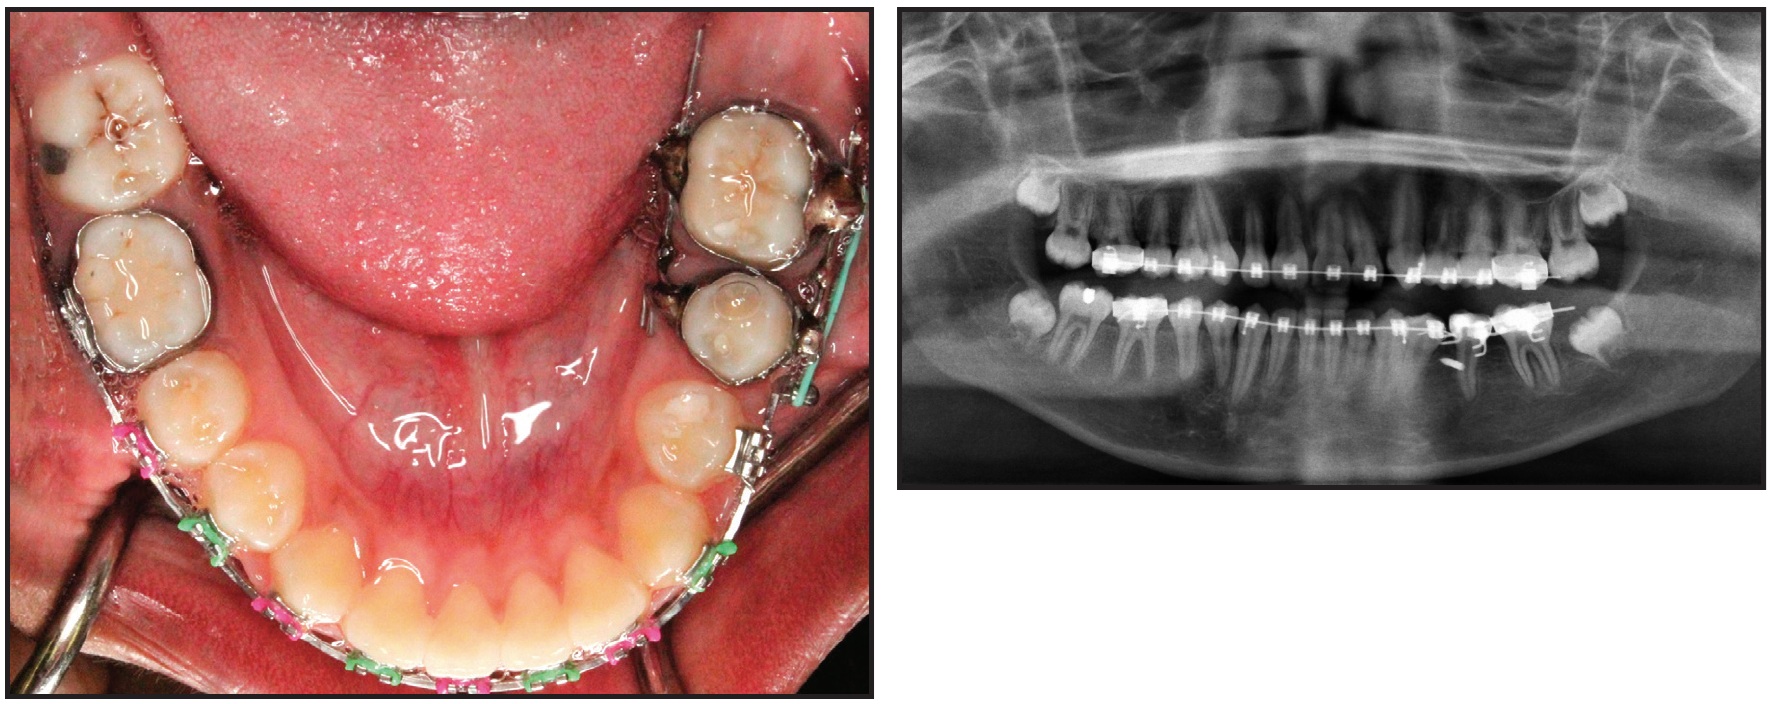

After .022" MBT* brackets were bonded in both arches, .016" nickel titanium archwires were placed for alignment. A sequence of .016" x .022" and .019" x .025" nickel titanium wires was followed, after about five months, by .019" x .025" stainless steel. At that point, the patient was referred for closed surgical exposure of the upper right central incisor. One month after exposure of the tooth, 50-75g of force was applied with an elastomeric thread to guide its eruption. After initial leveling and alignment in the mandibular arch, excluding the lower left second molar, an .019" x .025" beta titanium cantilever spring was inserted in the lower left second-molar tube and hooked between the canine and premolar (Fig. 5).

Fig. 5 After six months of treatment, with .019" × .025" stainless steel archwires in place, cantilever spring inserted in lower left second-molar tube and hooked between canine and premolar to upright mesially tipped second molar. Exposed upper right central incisor guided into arch using elastomeric thread.

The anchorage unit consisted of the entire mandibular archwire except for the left second molar. The intrusive cantilever spring was designed to exert 50g of intrusive force anteriorly and a distal tipback moment of 1,000-1,250g-mm on the mesially tipped molar (Fig. 6). After the lower left second molar had been uprighted for six months, 7-8mm of edentulous space could be seen between it and the second premolar (Fig. 7).

To further level and align the uprighted second molar with the rest of the lower arch, a continuous .016" x .022" nickel titanium archwire was placed. Three months later, an .019" x .025" stainless steel archwire was placed and a 1.8mm x 8mm mini-implant** was inserted interdentally between the lower left premolars. The lower left second-premolar bracket was removed, and bands were placed. A lower alginate impression was sent to the laboratory for fabrication of the previously described molar protraction appliance (Fig. 8).

Fig. 7 Edentulous lower left first-molar space after six months of uprighting second molar.